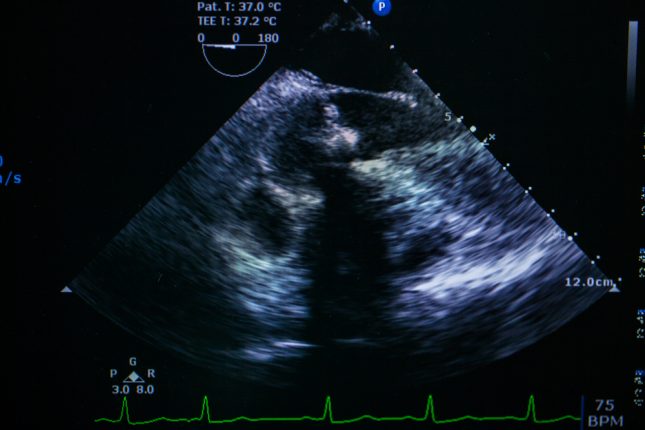

אקו-לב.-אילוסטרציה